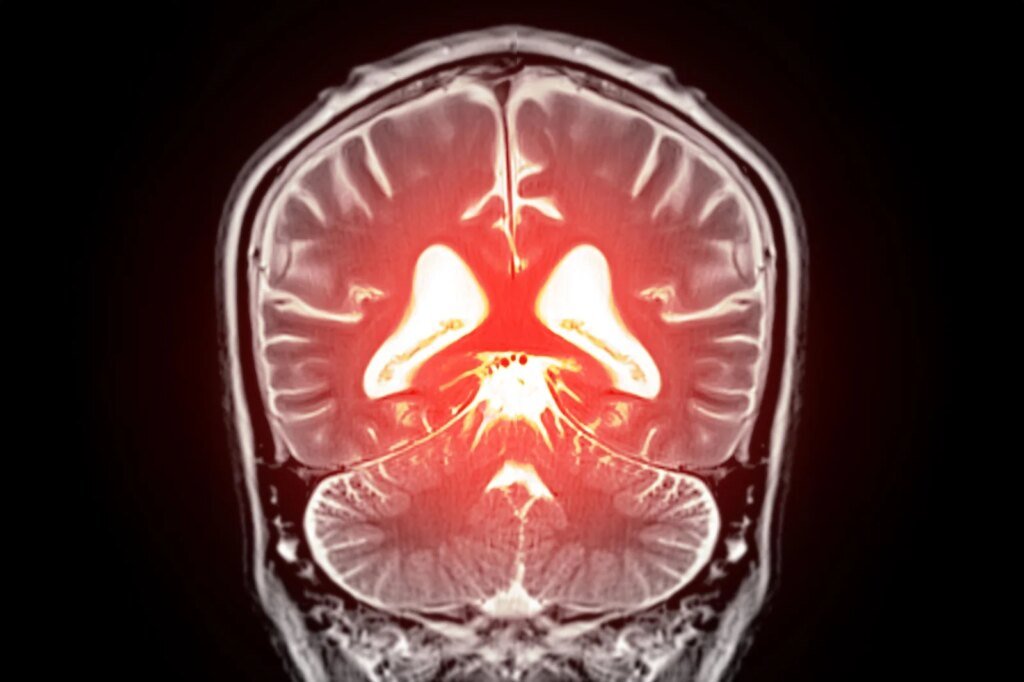

قد يؤدي استبدال الدهون المفقودة في الدماغ إلى تهدئة الأوعية الدموية المفرطة النشاط واستعادة تدفق الدم الصحي، مما يفتح طريقًا جديدًا نحو علاج الخرف.

بدأ يتبلور نهج جديد محتمل لعلاج انخفاض تدفق الدم في الدماغ وبعض أشكال الخرف. كشف علماء في جامعة فيرمونت، روبرت لارنر، دكتوراه في الطب بكلية الطب، تفاصيل جديدة حول كيفية تنظيم تدفق الدم في الدماغ وحددوا استراتيجية يمكن أن تساعد في تصحيح المشاكل في الأوعية الدموية في الدماغ. تم نشر بحثهم قبل السريري اليوم (22 ديسمبر) في وقائع الأكاديمية الوطنية للعلوميشير إلى أن استعادة الفسفوليبيد المفتقد في مجرى الدم قد يساعد في تطبيع تدفق الدم العقلي وتخفيف الأعراض المرتبطة بالخرف.

اكتشف العلماء أن PIP₂ يعمل عادةً كمكابح طبيعية لـ Piezo1. عندما تنخفض مستويات PIP₂، يصبح Piezo1 نشطًا بشكل مفرط، مما يعطل تدفق الدم الطبيعي في الدماغ. عندما أضاف الباحثون PIP₂ مرة أخرى إلى النظام، انخفض نشاط Piezo1 وتم استعادة تدفق الدم الصحي. تشير هذه النتائج إلى أن زيادة مستويات PIP₂ يمكن أن تمثل نهجًا علاجيًا جديدًا لتحسين الدورة الدموية في الدماغ ودعم وظائف المخ.